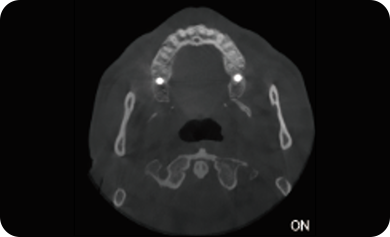

支持局部超清三维显示

局部超清显示、 移动视野摄片

可根据临床需求任意调整成像区域大小实现局部超清三维显示

临床样片